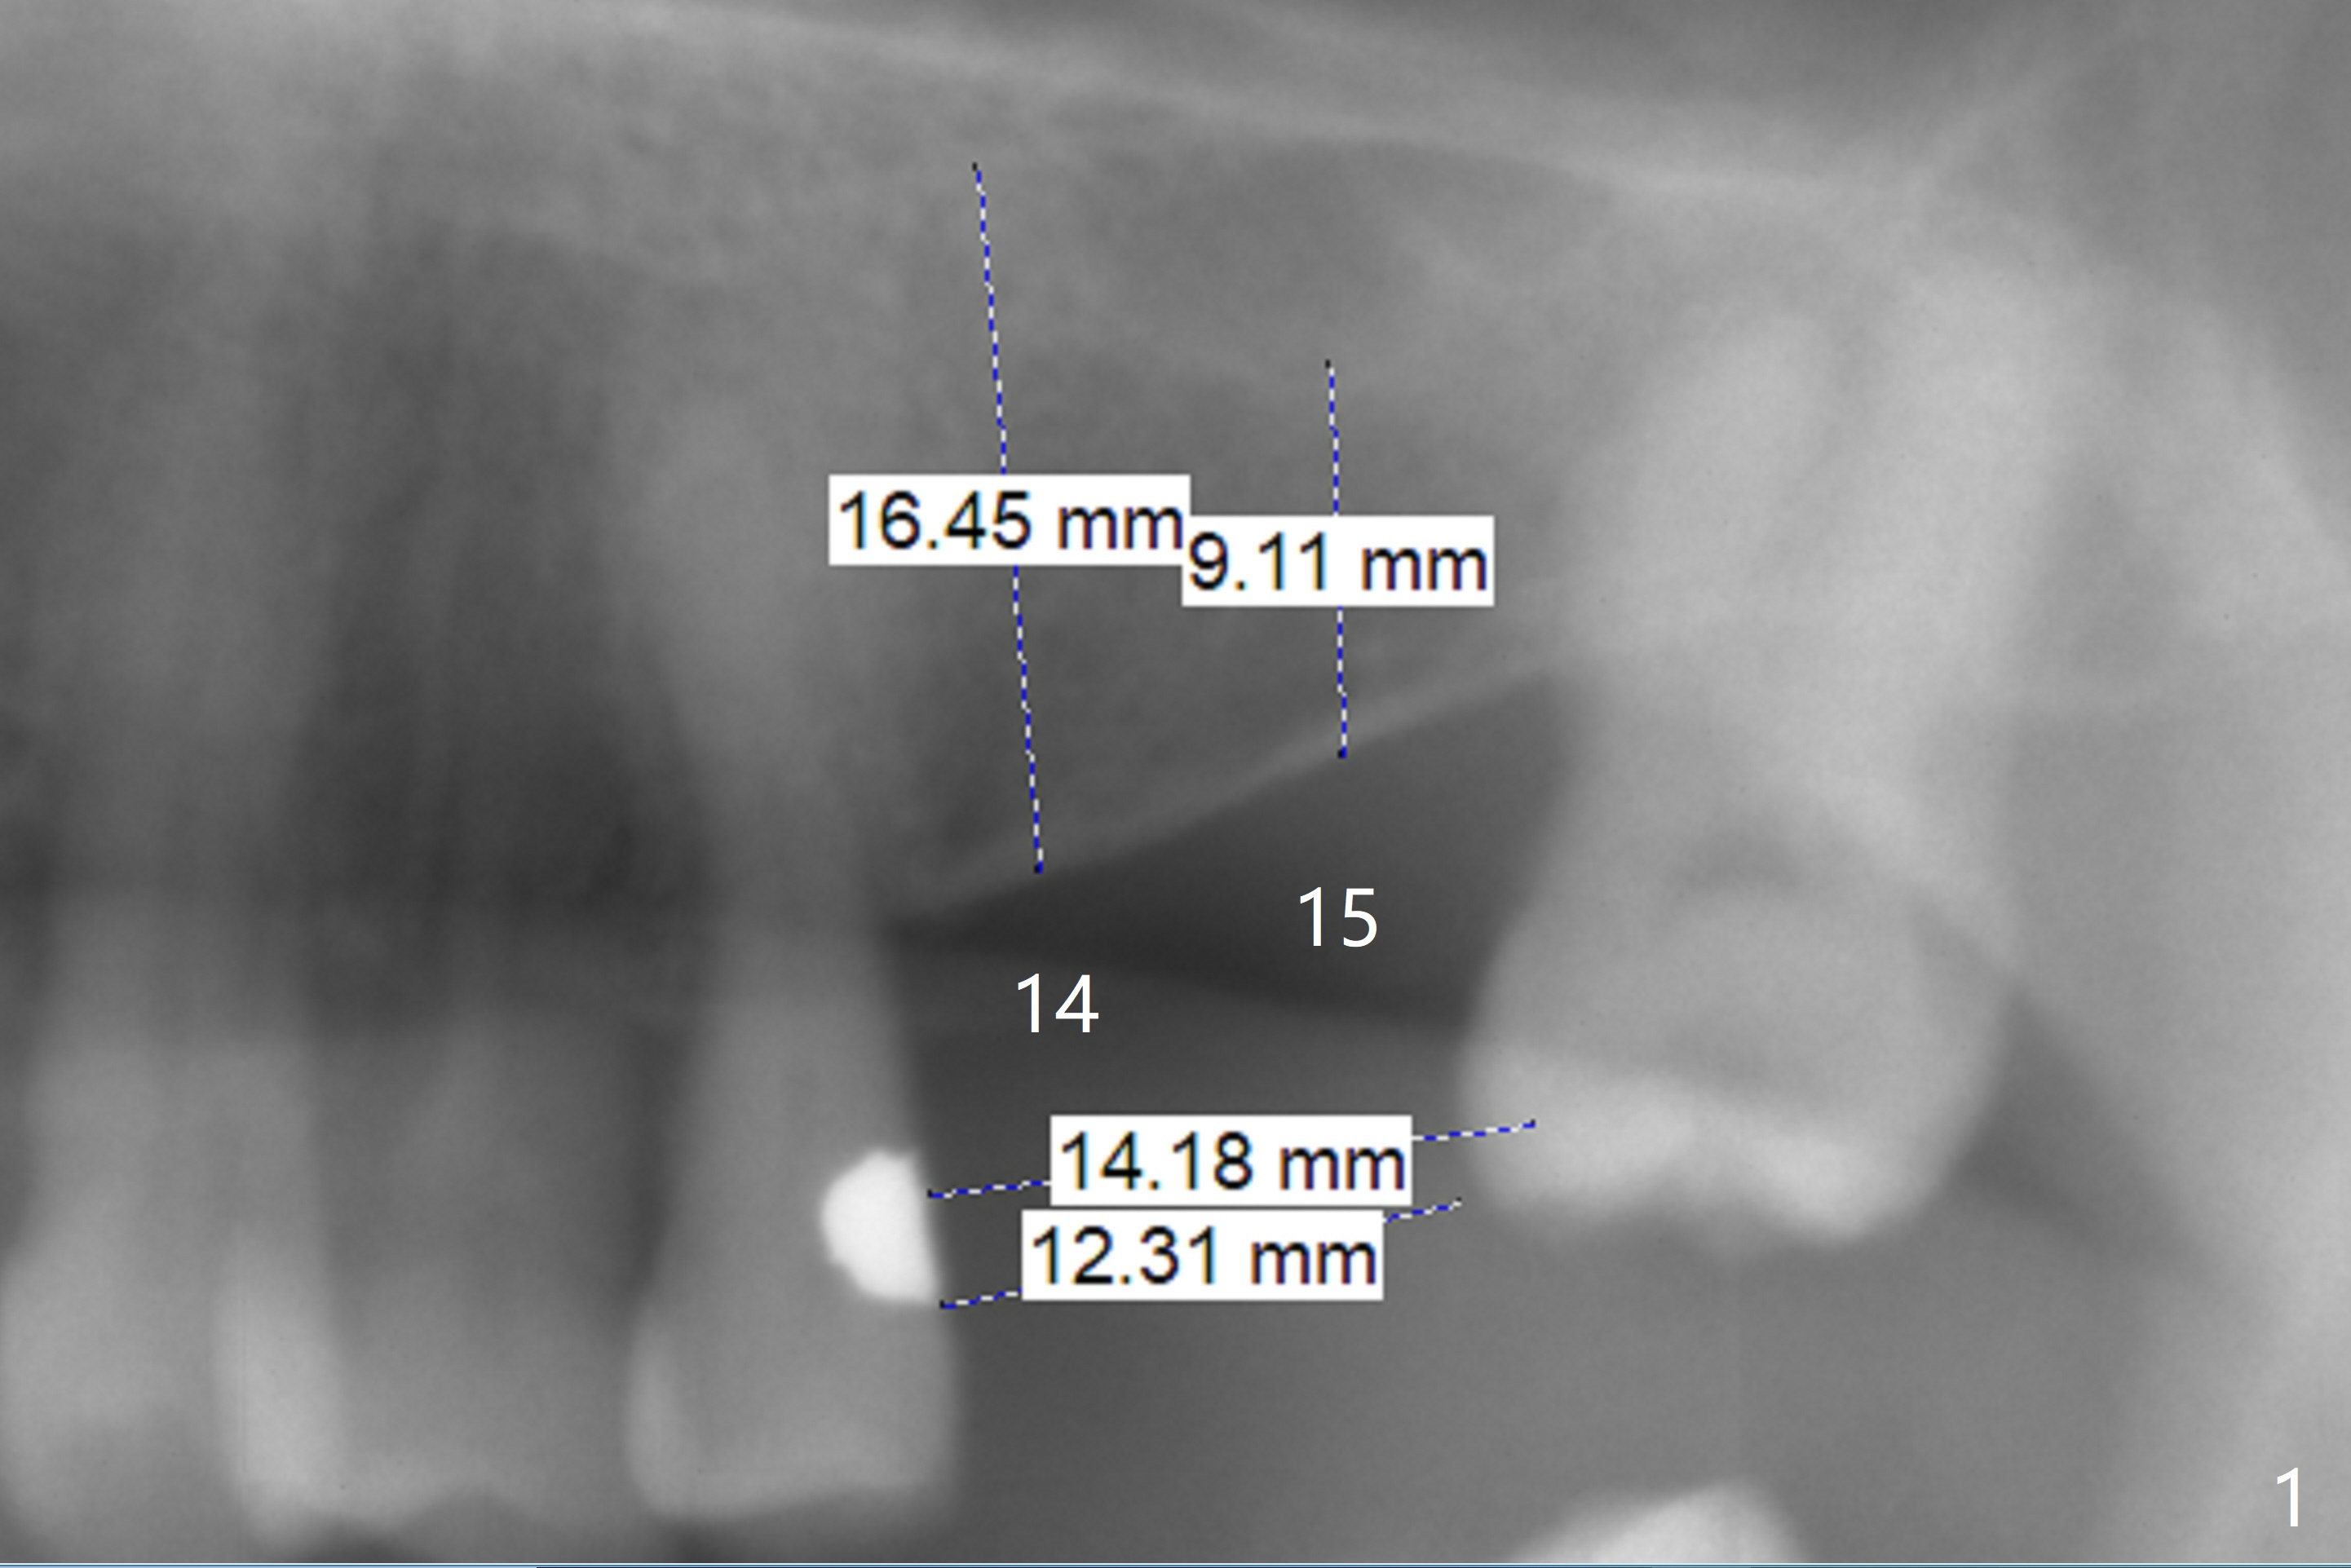

After implants at the lower incisors, the 67-year-old man requests implants at #14,15 (Fig.1). The mesiodistal edentulous space (12.31 mm) is wide one implant and apparently narrow for 2 ones. If the ridge is wide buccopalatally, consider one large or normal-sized implant. Otherwise use 2 of 1-piece 3 mm implants after mesial reduction of the tooth #16 (to 14.18 mm). Make the reduction before CT and impression for guide.